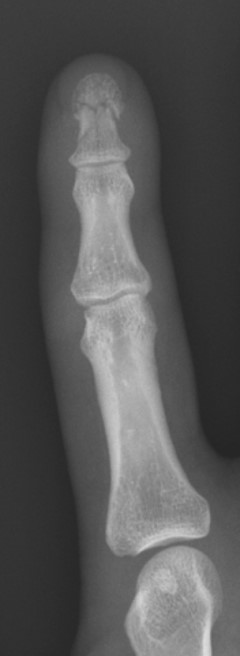

X-ray is required to confirm the diagnosis.

Photo source: Orthobullets